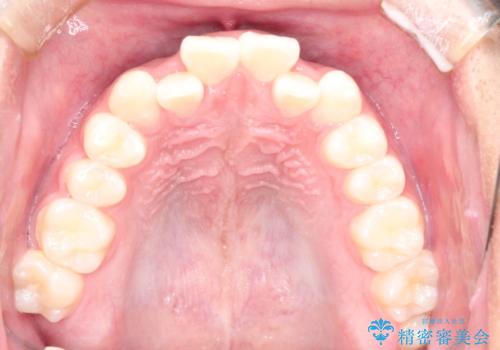

- 前歯のがたつきを主訴に来院されました。

上顎の前から2番目の歯の噛み合わせが反対になっていました。

抜歯矯正も考えられるケースでしたが、非抜歯での矯正を希望され、インビザラインにて治療することとなりました。

目立たずに矯正を終えることができ、患者様にも満足していただきました。